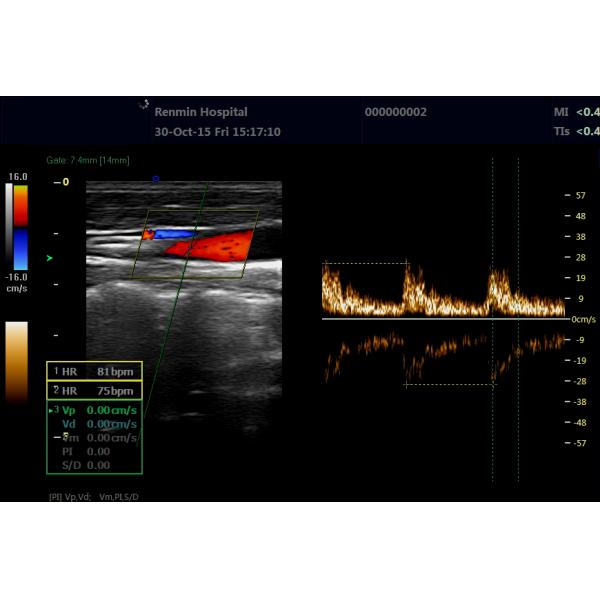

Product Name : Doppler Ultrasound Scanner

Type : Color Doppler

Full Digital Color Doppler System Instruments Portable Doppler Ultrasound Machine

*B/2B/4B/M/CFM/PDI/PW

*THI(Tissue Harmonic Imaging)

*Real-time 2D and Color Dual Mode.

*Real-time 2D and Doppler Double Synchronization.

*Real-time 2D ,Doppler and Color triple synchronization.

XF3600(E60) is an economical all-digital portable color doppler ultrasound diagnostic system launched by XianFeng company in 2016.

Small organs and Peripheral Blood Vessel Measurement and Analysis

The main measurement and analysis of vascular cross-sectional area, heart rate, per volume, flow per unit time, ejection time,stenosis rate, average velocity of blood flow, RI resistance index, PI pulsatile index.

Xianfeng Portable Doppler Ultrasound Machine CFM PDI Images |